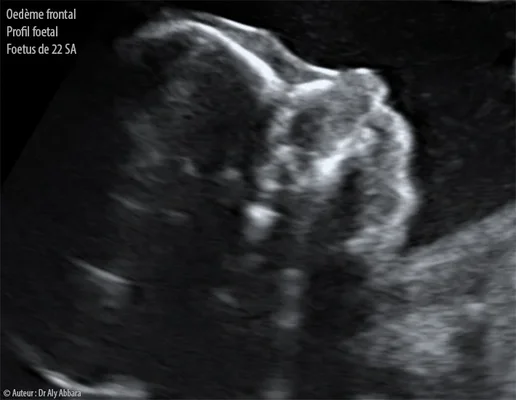

L'histoire commence au cours du troisième trimestre de grossesse. Rien ne laissait présager un drame. Pourtant, lors d'une échographie de contrôle, la sage-femme remarque une anomalie. L'inquiétude monte d'un cran lorsqu'on oriente la future maman vers le professeur Edgar Montoya, chef du pôle femme-mère-enfant au groupe hospitalier régional Mulhouse Sud-Alsace. Les examens révèlent une tumeur de 9 à 10 centimètres au niveau de la tête et du cou du fœtus. C'est énorme, surtout pour un être aussi petit.

Lors de cette consultation décisive, l'échographiste ne tarde pas à alerter l'équipe médicale. La masse est non seulement volumineuse, mais elle semble aussi très vascularisée. Pour les parents, l'annonce est un choc violent. On passe en quelques secondes de l'insouciance d'une grossesse épanouie à la perspective d'un combat pour la vie de leur enfant à naître. Le scanner et l'IRM confirment rapidement la gravité de la situation : la croissance de la tumeur est rapide et menace l'intégrité physique du fœtus.